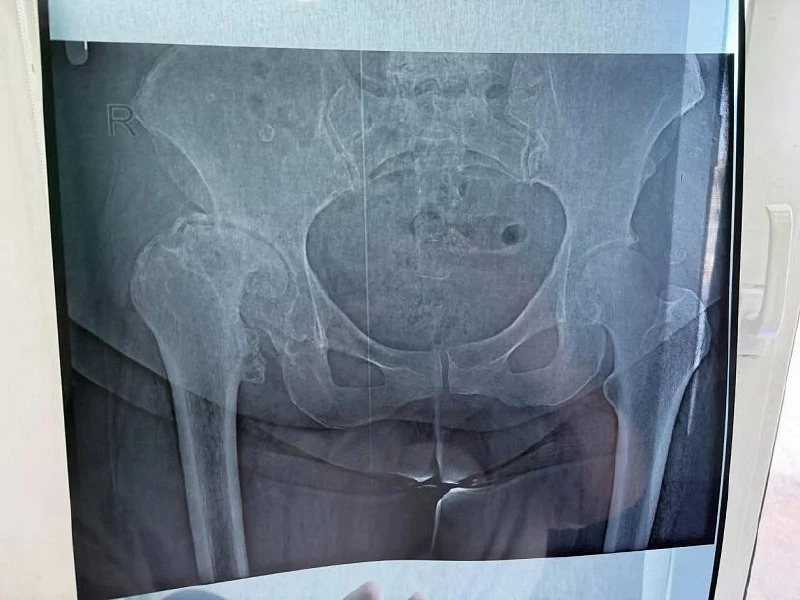

👨‍⚕️В Энгельсе у пациента с жалобами на тошноту выявили гигантские опухоли

В Саратовской области медики оперативно диагностировали заболевание у пожилого пациента.

В городскую клиническую больницу № 1 города Энгельса обратился 71-летний горожанин. Пациент жаловался на тошноту, слабость, дискомфорт в правом подреберье. Его госпитализировали в гастроэнтерологическое отделение.

МРТ выявило множественные гигантские образования печени, по признакам похожие на вторичное поражение. В анамнезе было указано, что мужчина получал оперативное лечение по поводу заболевания мочевого пузыря. После консилиума с врачами-урологами пенсионера отправили на МРТ органов малого таза.

«Было выявлено образования стенки мочевого пузыря с прорастанием в его полость. Больной незамедлительно направлен в Саратовский областной клинический онкологический диспансер, где в настоящее время проходит специализированное лечение», - пояснили в ЭКГБ.